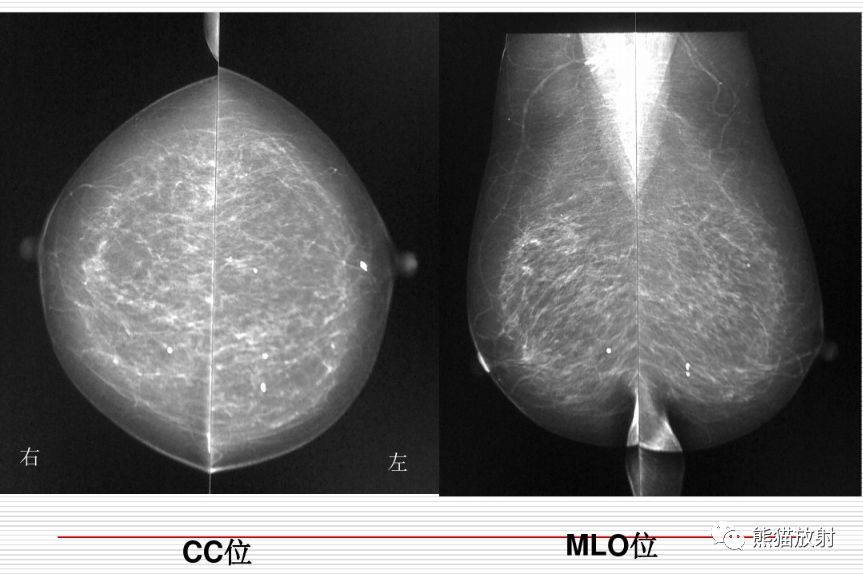

乳腺钼靶